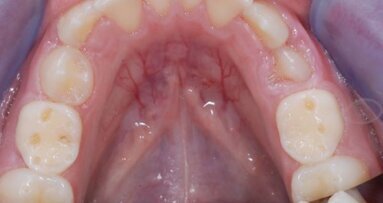

On je napomenuo da je veoma teško postaviti kliničku dijagnozu preosetljivosti s obzirom da osetljivo i neosetljivo tkivo slično izgledaju prilikom specijalističkog pregleda.

Opisao je i najšire prihvaćenu teoriju preosetljivosti – hidrodinamičku teoriju. Objašnjavajući hidrodinamički mehanizam zuba, pozvao se na istraživanje koje se bavilo proučavanjem osetljivog i neosetljivog zuba. Rezultati istraživanja su pokazali da unutar osetljivog zuba ima i do osam puta više dentinskih tubula, te da je njihov prečnik dva puta širi u odnosu na tubule neosetljivog zuba.

Ona je istakla uticaj preosetljivosti dentina na ponašanje pacijenata čiji je kvalitet života narušen ovim zdravstvenim stanjem. Ona se usredsredila na činjenicu da dentin mora da bude izložen kako bi nastala bolna preosetljivost, a da je izložen dentin uglavnom posledica povlačenja gingive, oštećenja gingive usled parodontopatije ili erozije zubne gleđi.